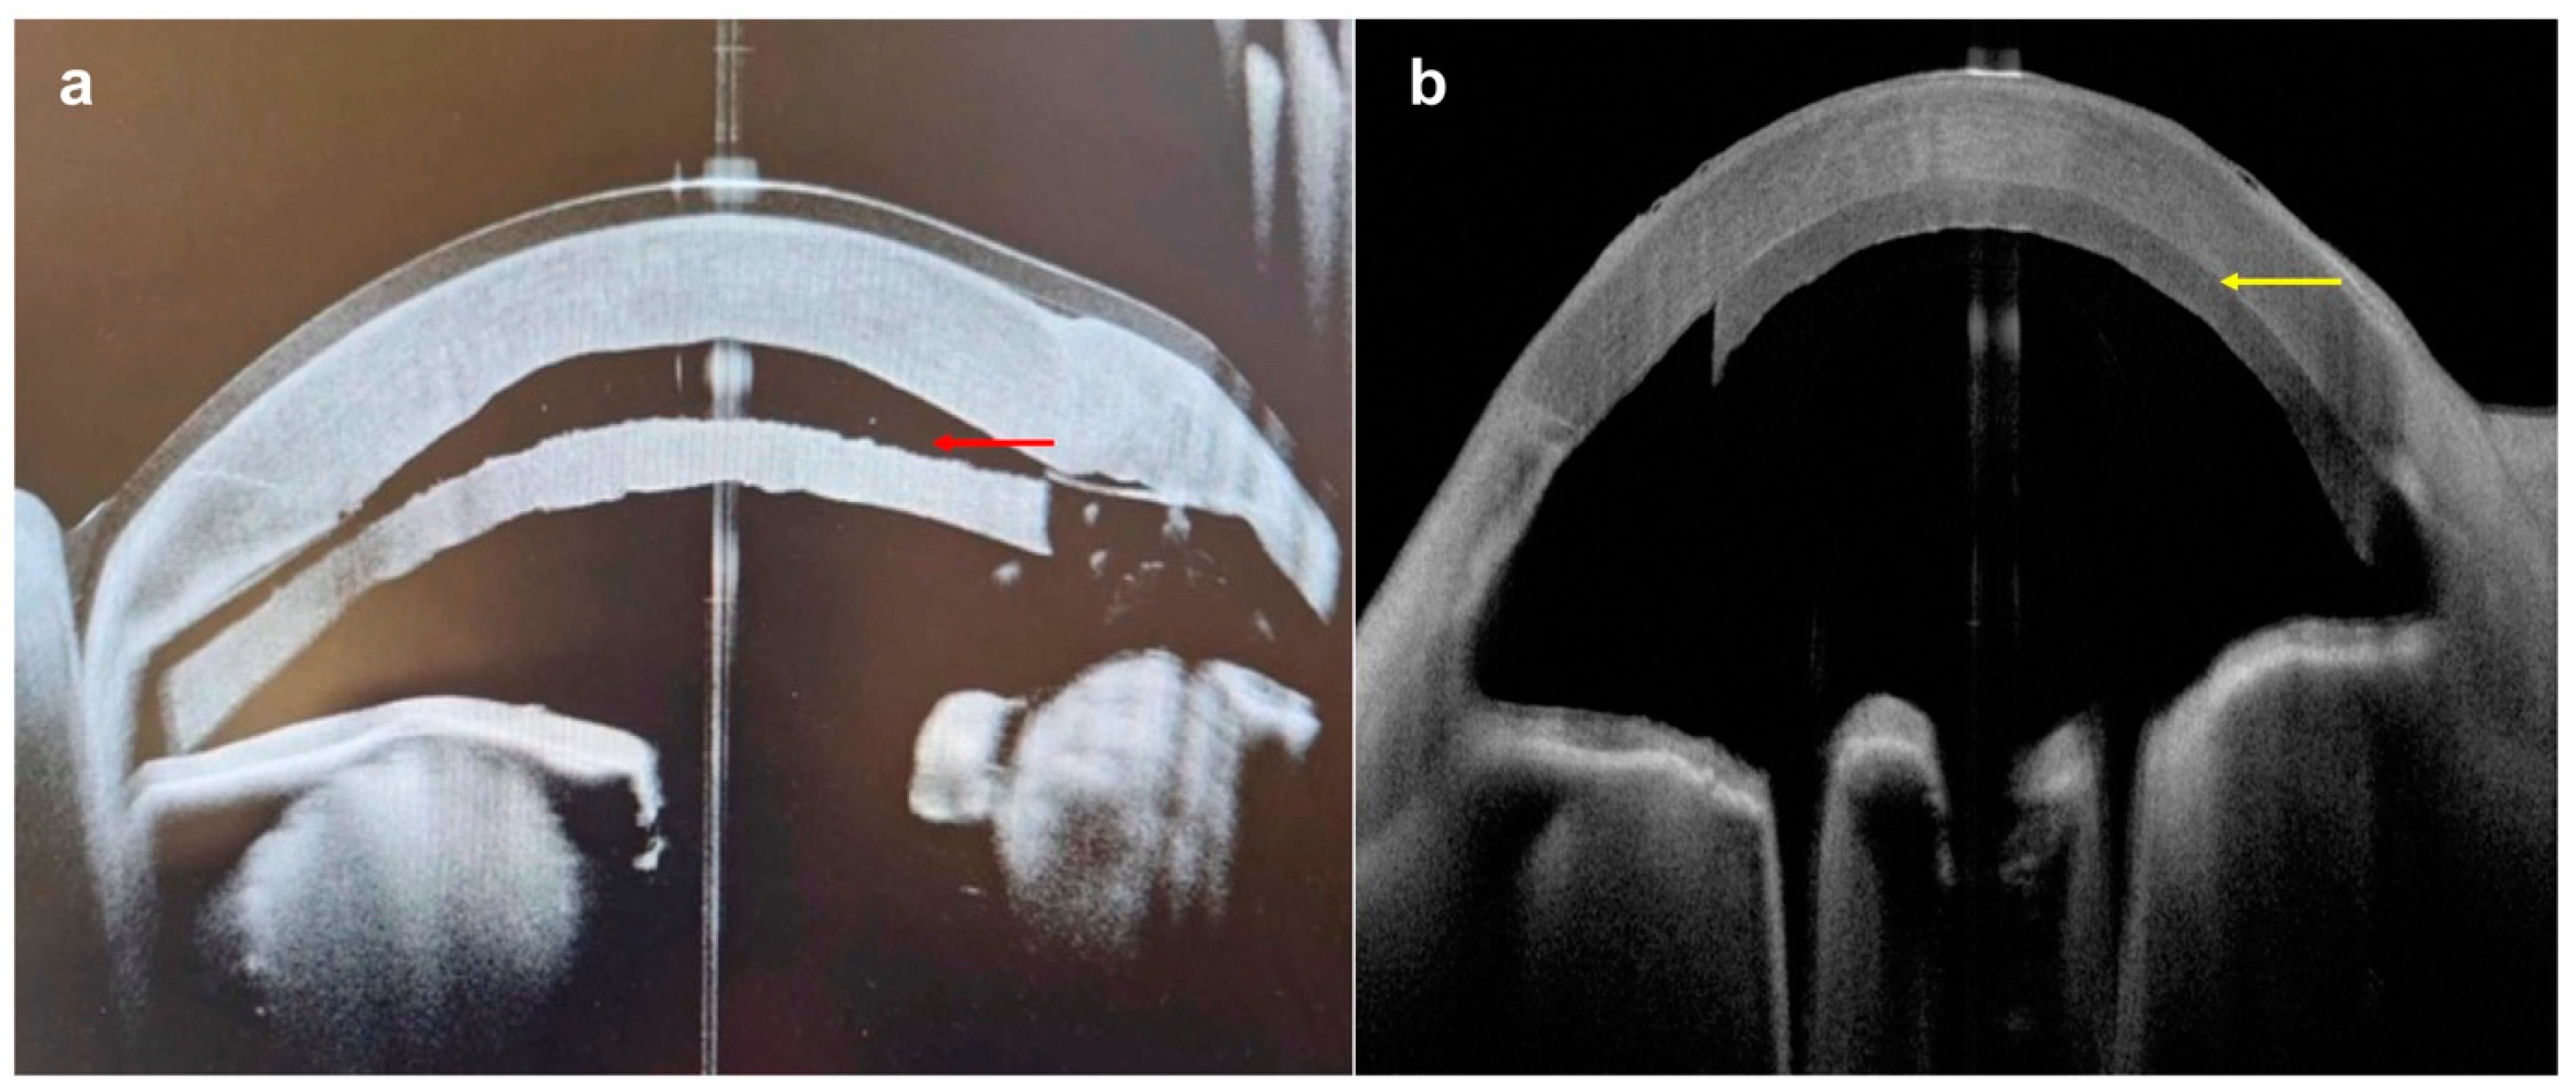

| Acute corneal hydrops |

|